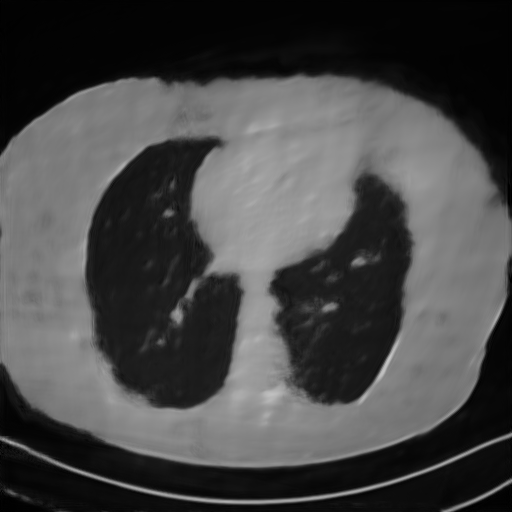

We further increase the noise level contained in the raw data to 10% white Gaussian noises and list the quantitative results in Table IV. It can be observed that the reconstruction performance of the TV model is poor in the case of high-level noises with PSNR dropping by 4 to 5 dB compared to the previous experiments. On the other hand, the performance of the learning-based methods is less sensitive to noises. The SIPID method relying on the sinogram interpolation works better than FBP-Unet. And the deep unrolling methods (i.e., PD-net, IFSR-net, SFSR-net) outperform the traditional iterative algorithm when the scanning range is limited and data is corrupted by noises. Similar to the previous experiments, compared with other deep learning algorithms, our LRIP-nets give the reconstruction results with higher PSNR and SSIM. Moreover, the low-resolution image obtained by the projection data down-sampled with rate 1/8 always gives the best reconstruction results with more than 2 dB PSNR and 0.05 SSIM increments compared to the PD-net. Fig. 6 illustrates the reconstructed images from different methodologies with scanning angular range of and 10% Gaussian noises. It can be seen that the both TV model and the FBP-Unet suffers from significant artifacts, which present distortions in the angular range of the missing scan. Other learning-based methods provides better visual qualities than FBP-Unet, and our LRIP-net1/8 still gives the best reconstruction result with correct boundaries and fine structures.

Fig. 7 manifests the reconstruction results of these methods with scanning angular of . It can be seen that both FBP and FBP-Unet produce serious artifacts within the range of missing angles. The TV model performs well in removing Poisson noises, but it can not handle the artifacts very well. Similarly, there left obvious artifacts on boundaries and different degrees of missing in visceral tissues of the reconstruction images obtained by the SIPID, PD-net and FSR-net. The visceral tissue and boundaries of our LRIP-net reconstructions are more intact and smoother, especially for the LRIP-net1/8 which gives the ideal boundaries. The observation becomes even apparent if we look at the zoom-in regions, where the LRIP-nets can produce results with fine structures. Therefore, we conclude that the low-resolution image prior can effectively improve the qualities of the limited-angle CT reconstruction.